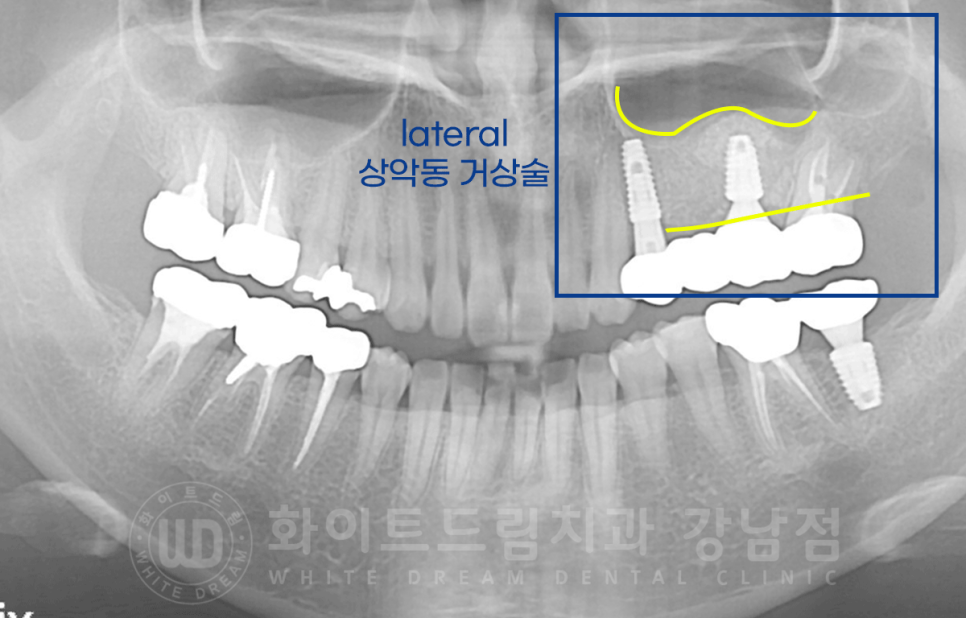

식립 후 x-ray 사진입니다.

▲ 임플란트가 식립 된 부위에 볼록하게 뼈이식이 진행된 것이 보이실 겁니다.

▼ 아래는 lateral 방식을 이용하여 뼈이식을 진행한 타 환자분의 x-ray인데요.

이식된 잇몸뼈 양의 차이가 눈에 보이실 겁니다.

무조건 잇몸뼈를 많이 이식하는 게 좋은 것 아닌가요?

임플란트는 잇몸뼈에 붙어 있어야 안정적으로 단단하게 고정이 됩니다.

하지만, 이미 충분히 임플란트가 고정될 만큼의 잇몸뼈가 있음에도 불구하고

불필요하게 과도한 뼈이식을 진행하는 것은 과잉진료에 속할 수 있습니다.

뼈이식 양이 불필요하게 늘어나면 환자분이 부담하는 비용도 늘어나겠죠?